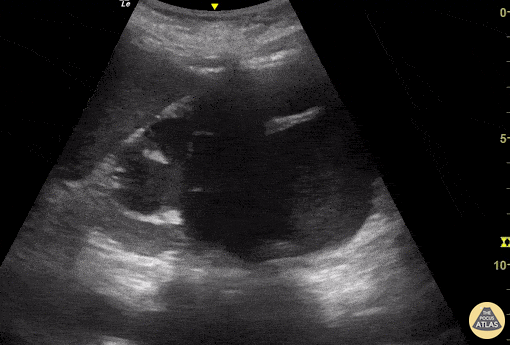

A 43-year-old female presented to the ED reporting fever and left-sided flank and low back pain. HPI was notable for recurrent urinary tract infections. POCUS performed on the Left Upper Quadrant revealed severe hydronephrosis, with hypdronephrotic collections in the region of the calyces resembling the outline of a bear’s paw (referred to as “bear paw sign”). Subsequent abdominal CT confirmed severe hydronephrosis secondary to stenosis of the ureteroplevic junction (UPJ). Josiane Almeida